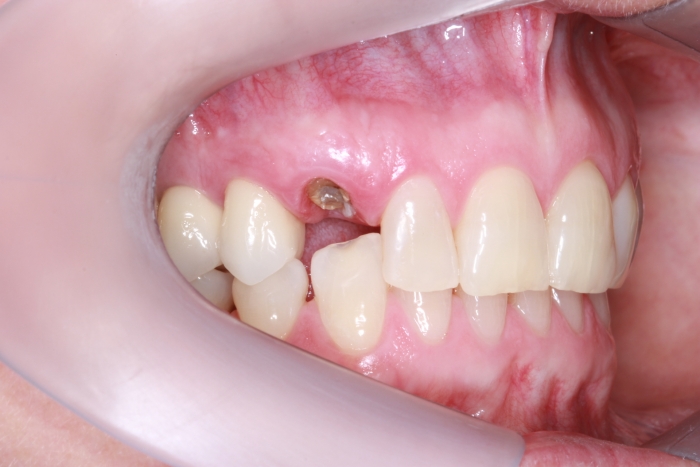

Foto lateral pré-cirurgica 03-10-16 - Clínica Cliniface

Foto lateral pré-cirurgica 03-10-16